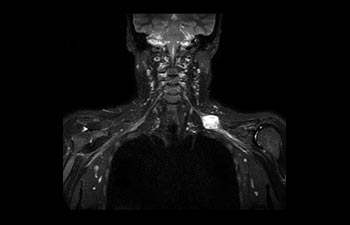

Sehen Sie selbst, was die ersten Nutzer von Ingenia Prodiva 1.5T über ihre Erfahrungen mit dem System und dessen Auswirkung auf ihre radiologische Praxis berichten.

Finden Sie die richtigen klinischen Applikationen für Ihre Anforderungen